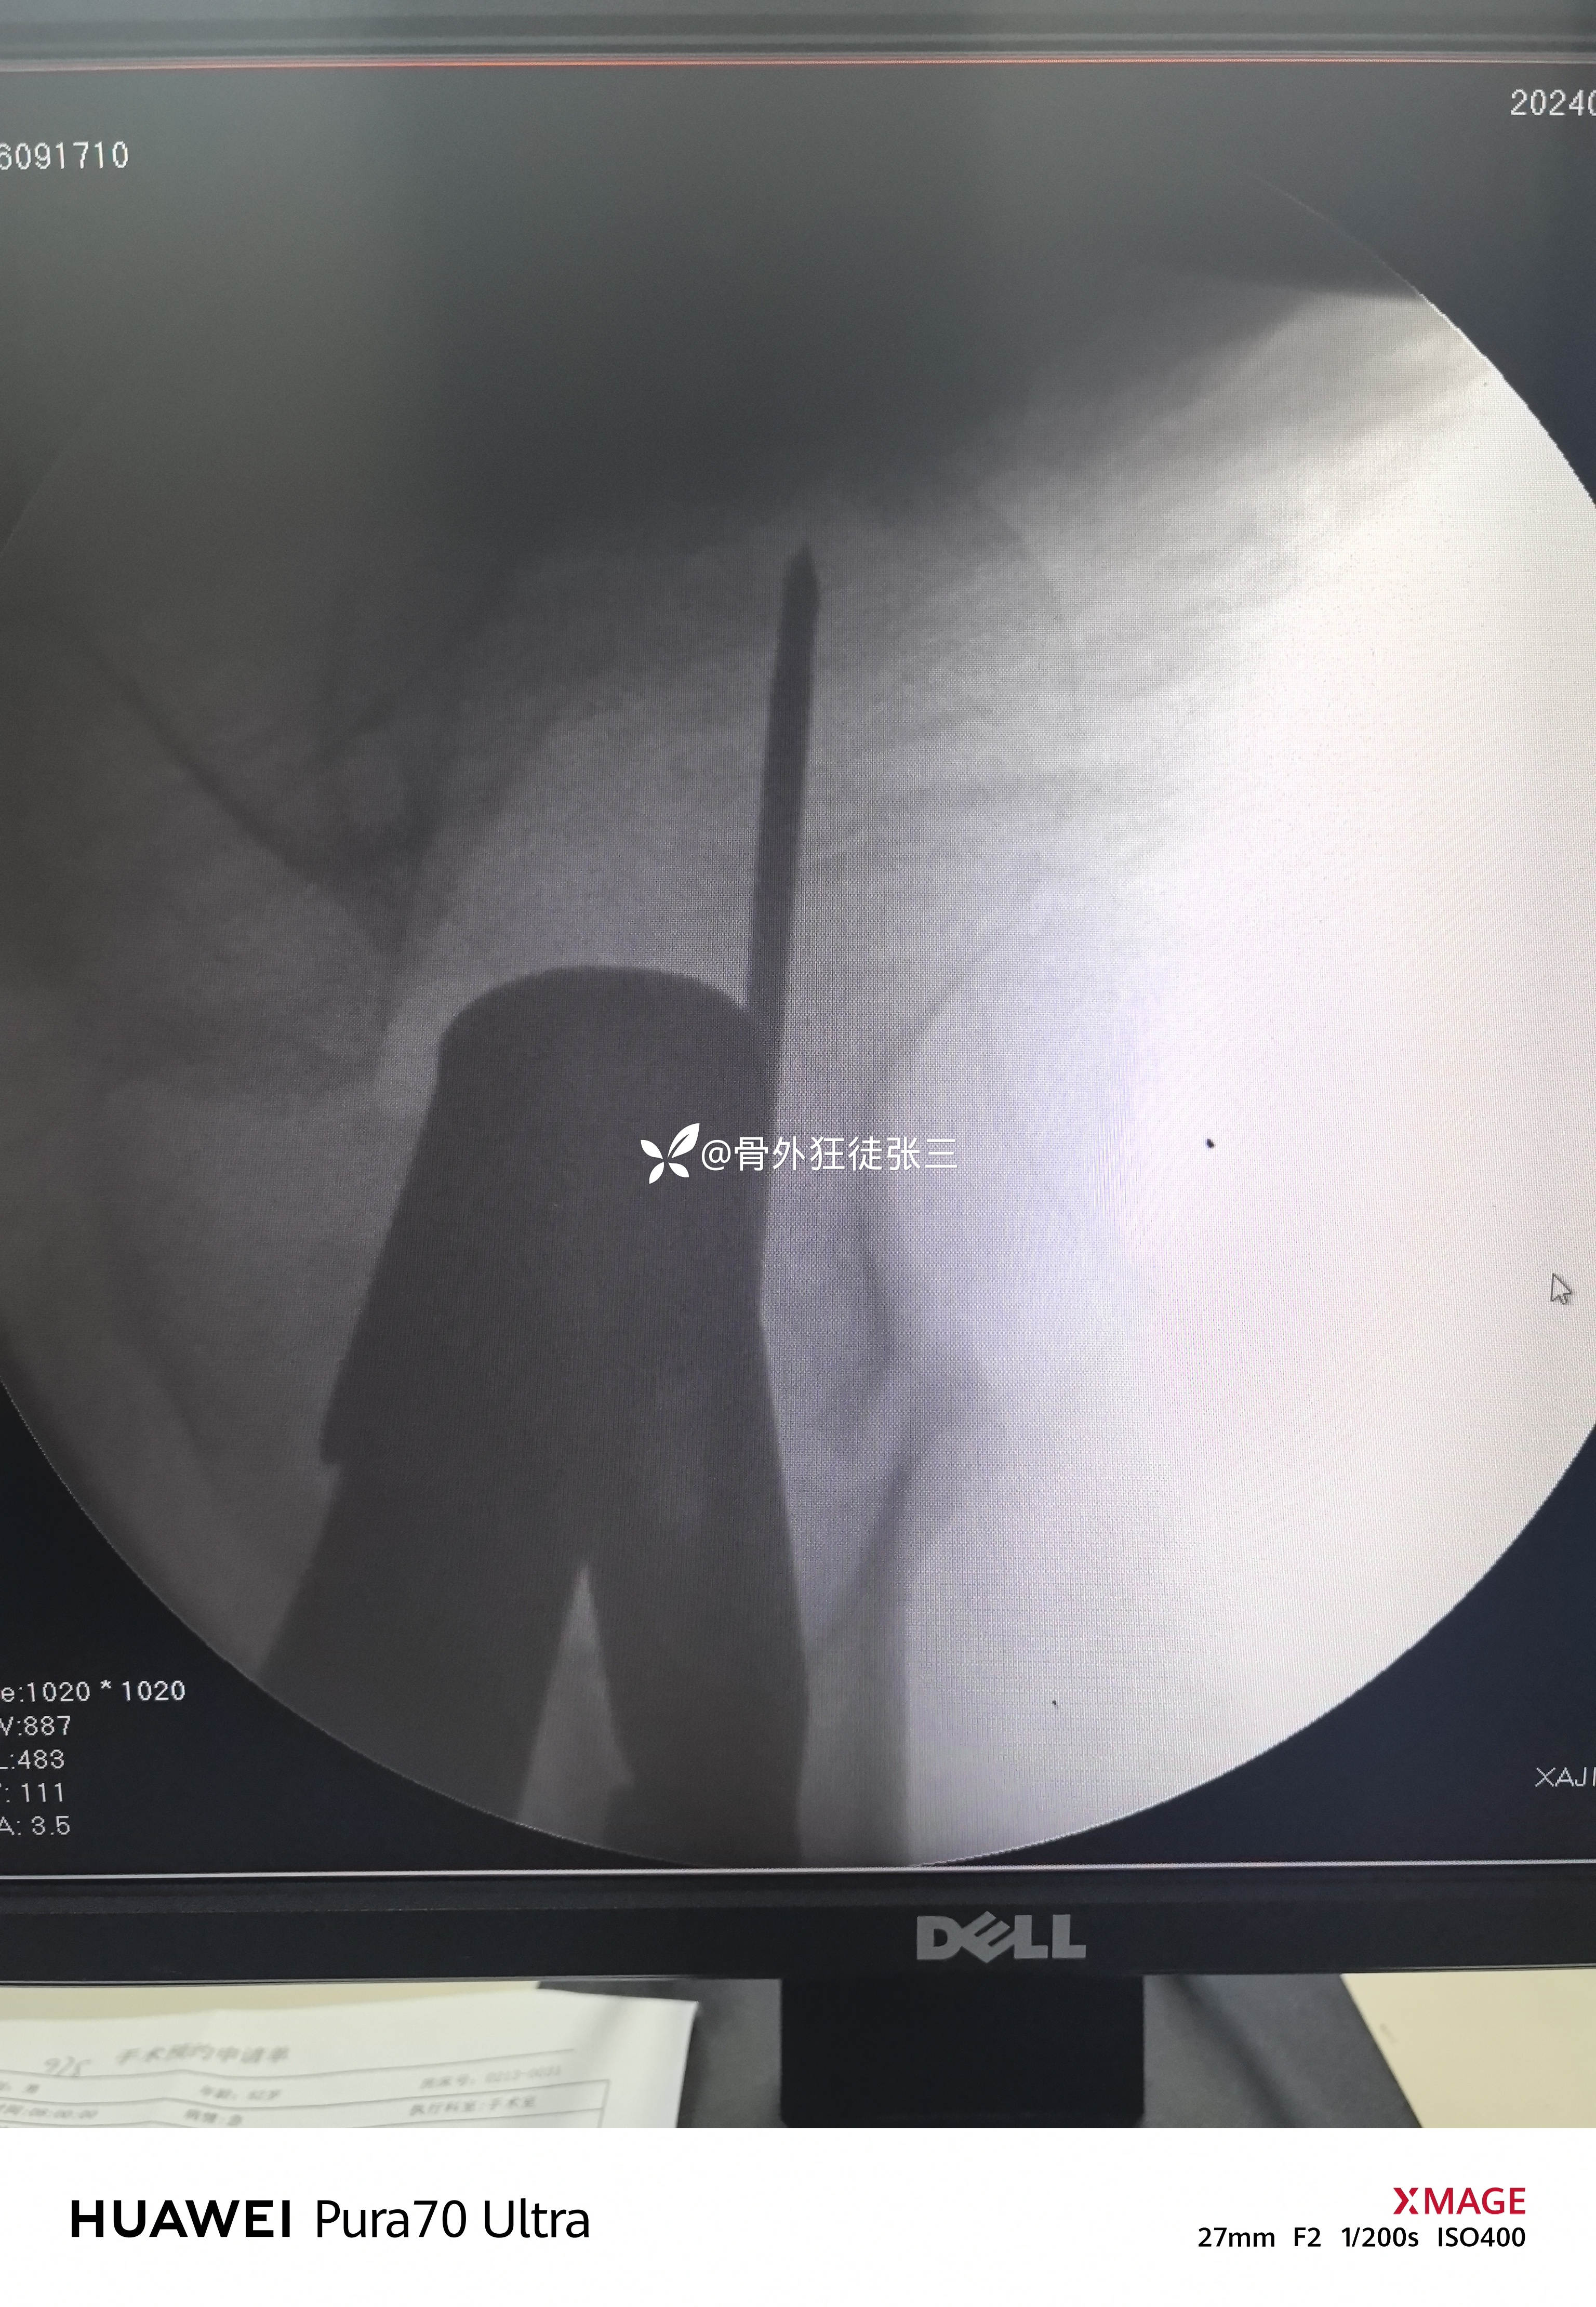

牵开器——透视正侧位——切口——确定进针点——铰刀开口——开口钻开口——金手指——导针置入——直接使用170 mmX12 mm主钉插入——调整前倾主钉深度和前倾——透视正位中下1/3,侧位基本居中——远端锁钉——近端锁尾端尾帽,——再次透视正、侧、蛙位——冲洗、缝合1-1-3 ——09:37-10:16 ——40分钟手术结束,透视16次,每次约一分钟,手术操作20分钟。